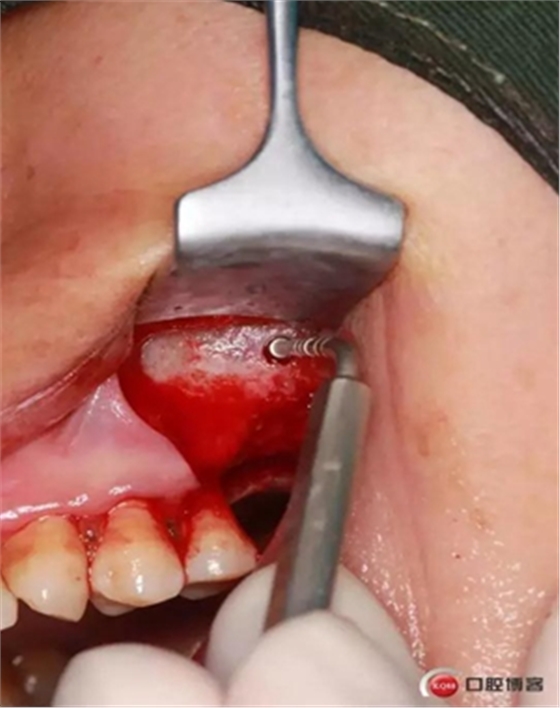

大家好,我是梁老師的助理小依。由于梁老師每天手術(shù)檔期安排較滿,加上經(jīng)常出差講課,沒有時間整理病例 。為了方便大家更及時的了解梁老師最新手術(shù)動態(tài),以后將由我為大家整理并推送梁老師最新經(jīng)典案例。案例文字旁白少,但圖片會盡量完整展示手術(shù)全過程,供大家學(xué)習(xí)參考。有任何問題,可以留言,梁老師會親自為大家解答。感謝大家對梁老師的支持和關(guān)注!